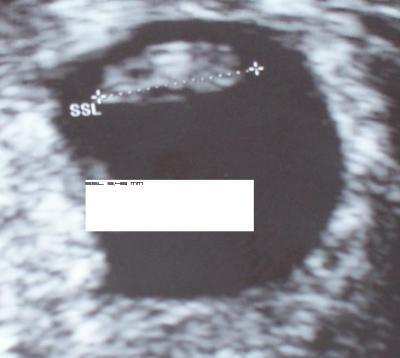

2. Bild 30.4.

Bild zu

hey sieht doch gut aus!